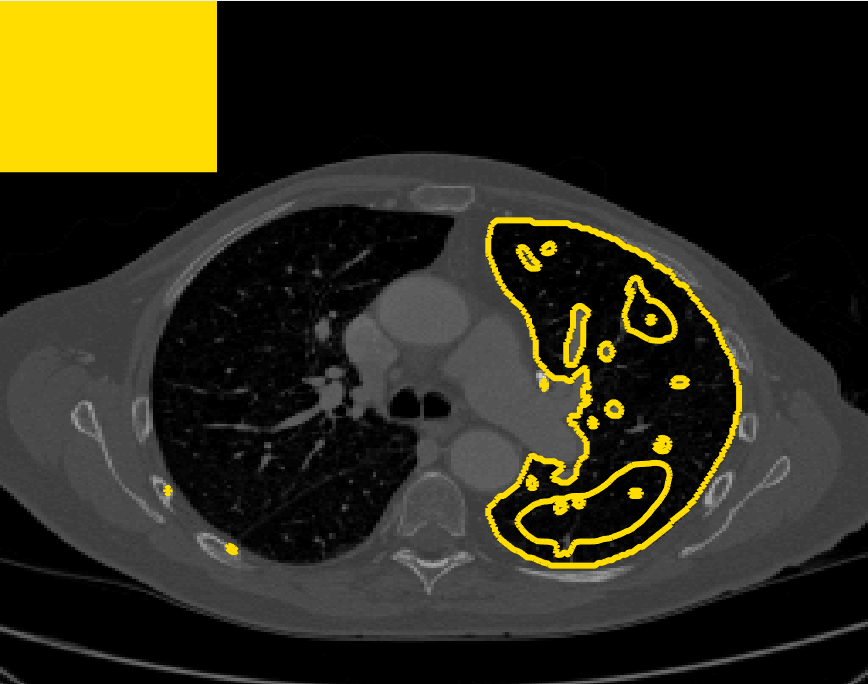

The motivation for this work comes from observing contradictions in using piecewise-constant intensity fitting terms in selective segmentation. Whilst good results are possible with this approach, the exceptional cases lead to severe limitations in practice. This is quite common in medical imaging as demonstrated in Fig. 1, where the target foreground has a low intensity. Given that the corresponding background includes large regions of low intensity, the optimal average intensities for this segmentation problem are and . For cases where , we see that by (1), almost everywhere in the domain . This means that it is very difficult to achieve an adequate result, without an over-reliance on the user input or parameter selection.

for and as defined in (33). This is consistent with respect to the intensities of the observed object and the concept of selective segmentation. In Fig. 3 we see the difference between CV and the proposed fitting terms for given user input on a CT image. For the CT image, the CV fitting terms are near 0 within the target region. This is despite there being a distinct homogeneous area with good contrast on the boundary. This illustrates the problem we are aiming to overcome. With the proposed fitting term this phenomenon should be avoided in cases like this. By defining as in (33) there is no contradiction if the foreground and background intensities of the target region are similar.